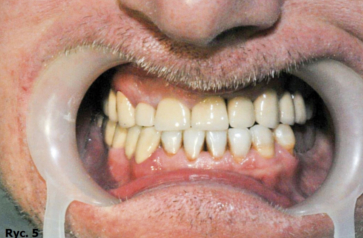

Pacjent B.J., lat 45, zgłosił się do gabinetu w celu poprawy estetyki i uzupełnienia braków zębowych. W badaniu zewnątrzustnym zaobserwowano wysunięcie bródki, wygładzenie bruzdy bródkowo wargowej, pacjent miał charakterystyczne wzmożone napięcie warg i kłopoty z wymową niektórych głosek. W badaniu wewnątrzustnym stwierdzono odwrotne zachodzenie zębów siecznych, zęby ustawione w III klasie Angle’a. Wynik dodatni testu czynnościowego bez poprawy rysów twarzy pozwolił postawić rozpoznanie: przodozgryz całkowity (ryc. 1, 2, 3).

Rozpoczęto od leczenia zachowawczego, w następnym etapie oszlifowano zęby górne pod korony i mosty protetyczne. Przy szlifowaniu zwrócono szczególną uwagę, by oś długa oszlifowanego kikuta zęba umożliwiła technikowi wykonującemu przyszłe uzupełnienie protetyczne ustawienie zębów w uzupełnieniu w zgryzie prostym. Zarówno uzupełnienia tymczasowe, jak i ostateczne ustawiono w zgryzie prostym. Widoczny brak w łuku dolnym po stronie lewej zostanie w najbliższym czasie uzupełniony koronami na implantach zębowych (ryc. 5, 6).